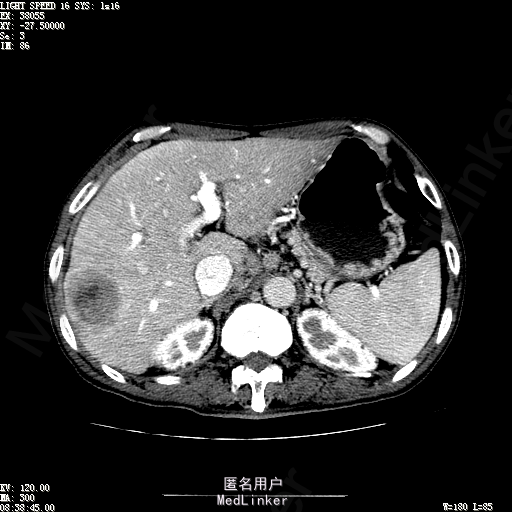

查体:体温36.3℃,脉搏76次/分,呼吸18次/分,血压120/80mmHg。神志清晰,肝病面容,皮肤粘膜颜色正常无黄染,全身皮肤未见皮疹、瘀点及紫癜,肝掌阳性,未见蜘蛛痣,浅表淋巴结未触及。巩膜无黄染,结膜正常。双肺呼吸音清,无胸膜摩擦音。心率:76次/分,心律齐,心音正常,无杂音,无心包摩擦音。腹平坦,无腹壁静脉曲张,未见胃肠型及蠕动波,双侧腹股沟可见手术瘢痕,脐部正常。触诊:无压及痛反跳痛,无腹肌紧张,无腹部包块。肝脾肋下未触及,Murphy征阴性,肾未触及,移动性浊音阴性。肝肾区叩击痛阴性,无脾区叩击痛。听诊:肠鸣音正常,4次/分,无气过水声。脊柱无侧弯,脊柱活动度正常,棘突正常,四肢正常,关节正常,无下肢水肿,无下肢静脉曲张,无杵状指趾。扑翼样震颤阴性。 门诊化验ALT9U/L,AST21U/L,HBVDNA<1.0E+03IU/mL,HBsAg1138IU/mL,WBC6.2x10^9/L,RBC3.92x10^12/L,PLT167x10^9/L,AFP28.95ng/ml,AFU 29U/L,彩超示肝右叶肝回声,大小约5.1*3.5cm,Fibroscan:脂肪变:163硬度10.8。 CT如下图

诊断:1、乙肝肝硬化 活动性 代偿期 原发性肝癌 2、胃溃疡 3、十二指肠球部溃疡 处理:血管介入治疗:手术者术前查看患者相关情况:化验回报:血细胞分析(五分类):*白细胞计数 8.1 10^9/L、*红细胞计数 4.00 10^12/L↓、*血小板计数 202.0 10^9/L、*血红蛋白 136 g/L,肝功酶谱:*丙氨酸氨基转移酶 5 U/L、天门冬氨酸氨基转移酶 22 U/L、*白蛋白 37.6 g/L、*总胆红素 17.8 umol/L,肾功能检测:*尿素 5.79 mmol/L、*肌酐 67.1 umol/L,凝血五项:凝血酶原时间 10.7 秒↓、凝血酶原百分活动度 93.3 %,甲胎蛋白测定:甲胎蛋白 30.30 ng/mL↑。患者病情平稳,今日术前准备,签署相关文件。 手术简要经过:患者平卧位,以右侧腹股沟区为中心常规消毒、铺巾、利多卡因局麻。改良Seldinger法逆行穿刺右侧股动脉成功,置入5F血管鞘。经血管鞘造影,见髂外动脉明显迂曲,经鞘送入超滑导丝,退出原5F血管鞘,换入5F长25厘米血管鞘。沿导丝送入肝管,将管头送入腹腔干,进一步送至肝右动脉。经正位、右前斜30°造影,明确肝右叶膈顶一处较大肿瘤染色,S5段一处较小肿瘤染色。以微导管超选S6段肝动脉干,经多角度造影明确为肿瘤供血动脉,注入混悬液(碘化油10毫升+雷替曲塞2毫克)3毫升,明胶海绵颗粒1/12支。再以微导管超选S7段肝动脉干,造影明确为肿瘤供血动脉,注入混悬液2毫升,明胶海绵颗粒1/20支。再以微导管超选S8段分支,造影明确为肿瘤供血动脉,注入混悬液2.8毫升,明胶海绵颗粒1/12支。再以微导管超选S5段肝动脉分支,造影明确为较小肿瘤供血动脉,注入混悬液0.8毫升,明胶海绵颗粒1/30支。退出微导管。经肝右动脉注入奥沙利铂100毫克。退出肝管。拔出血管鞘,局部压迫5分钟。加压包扎。